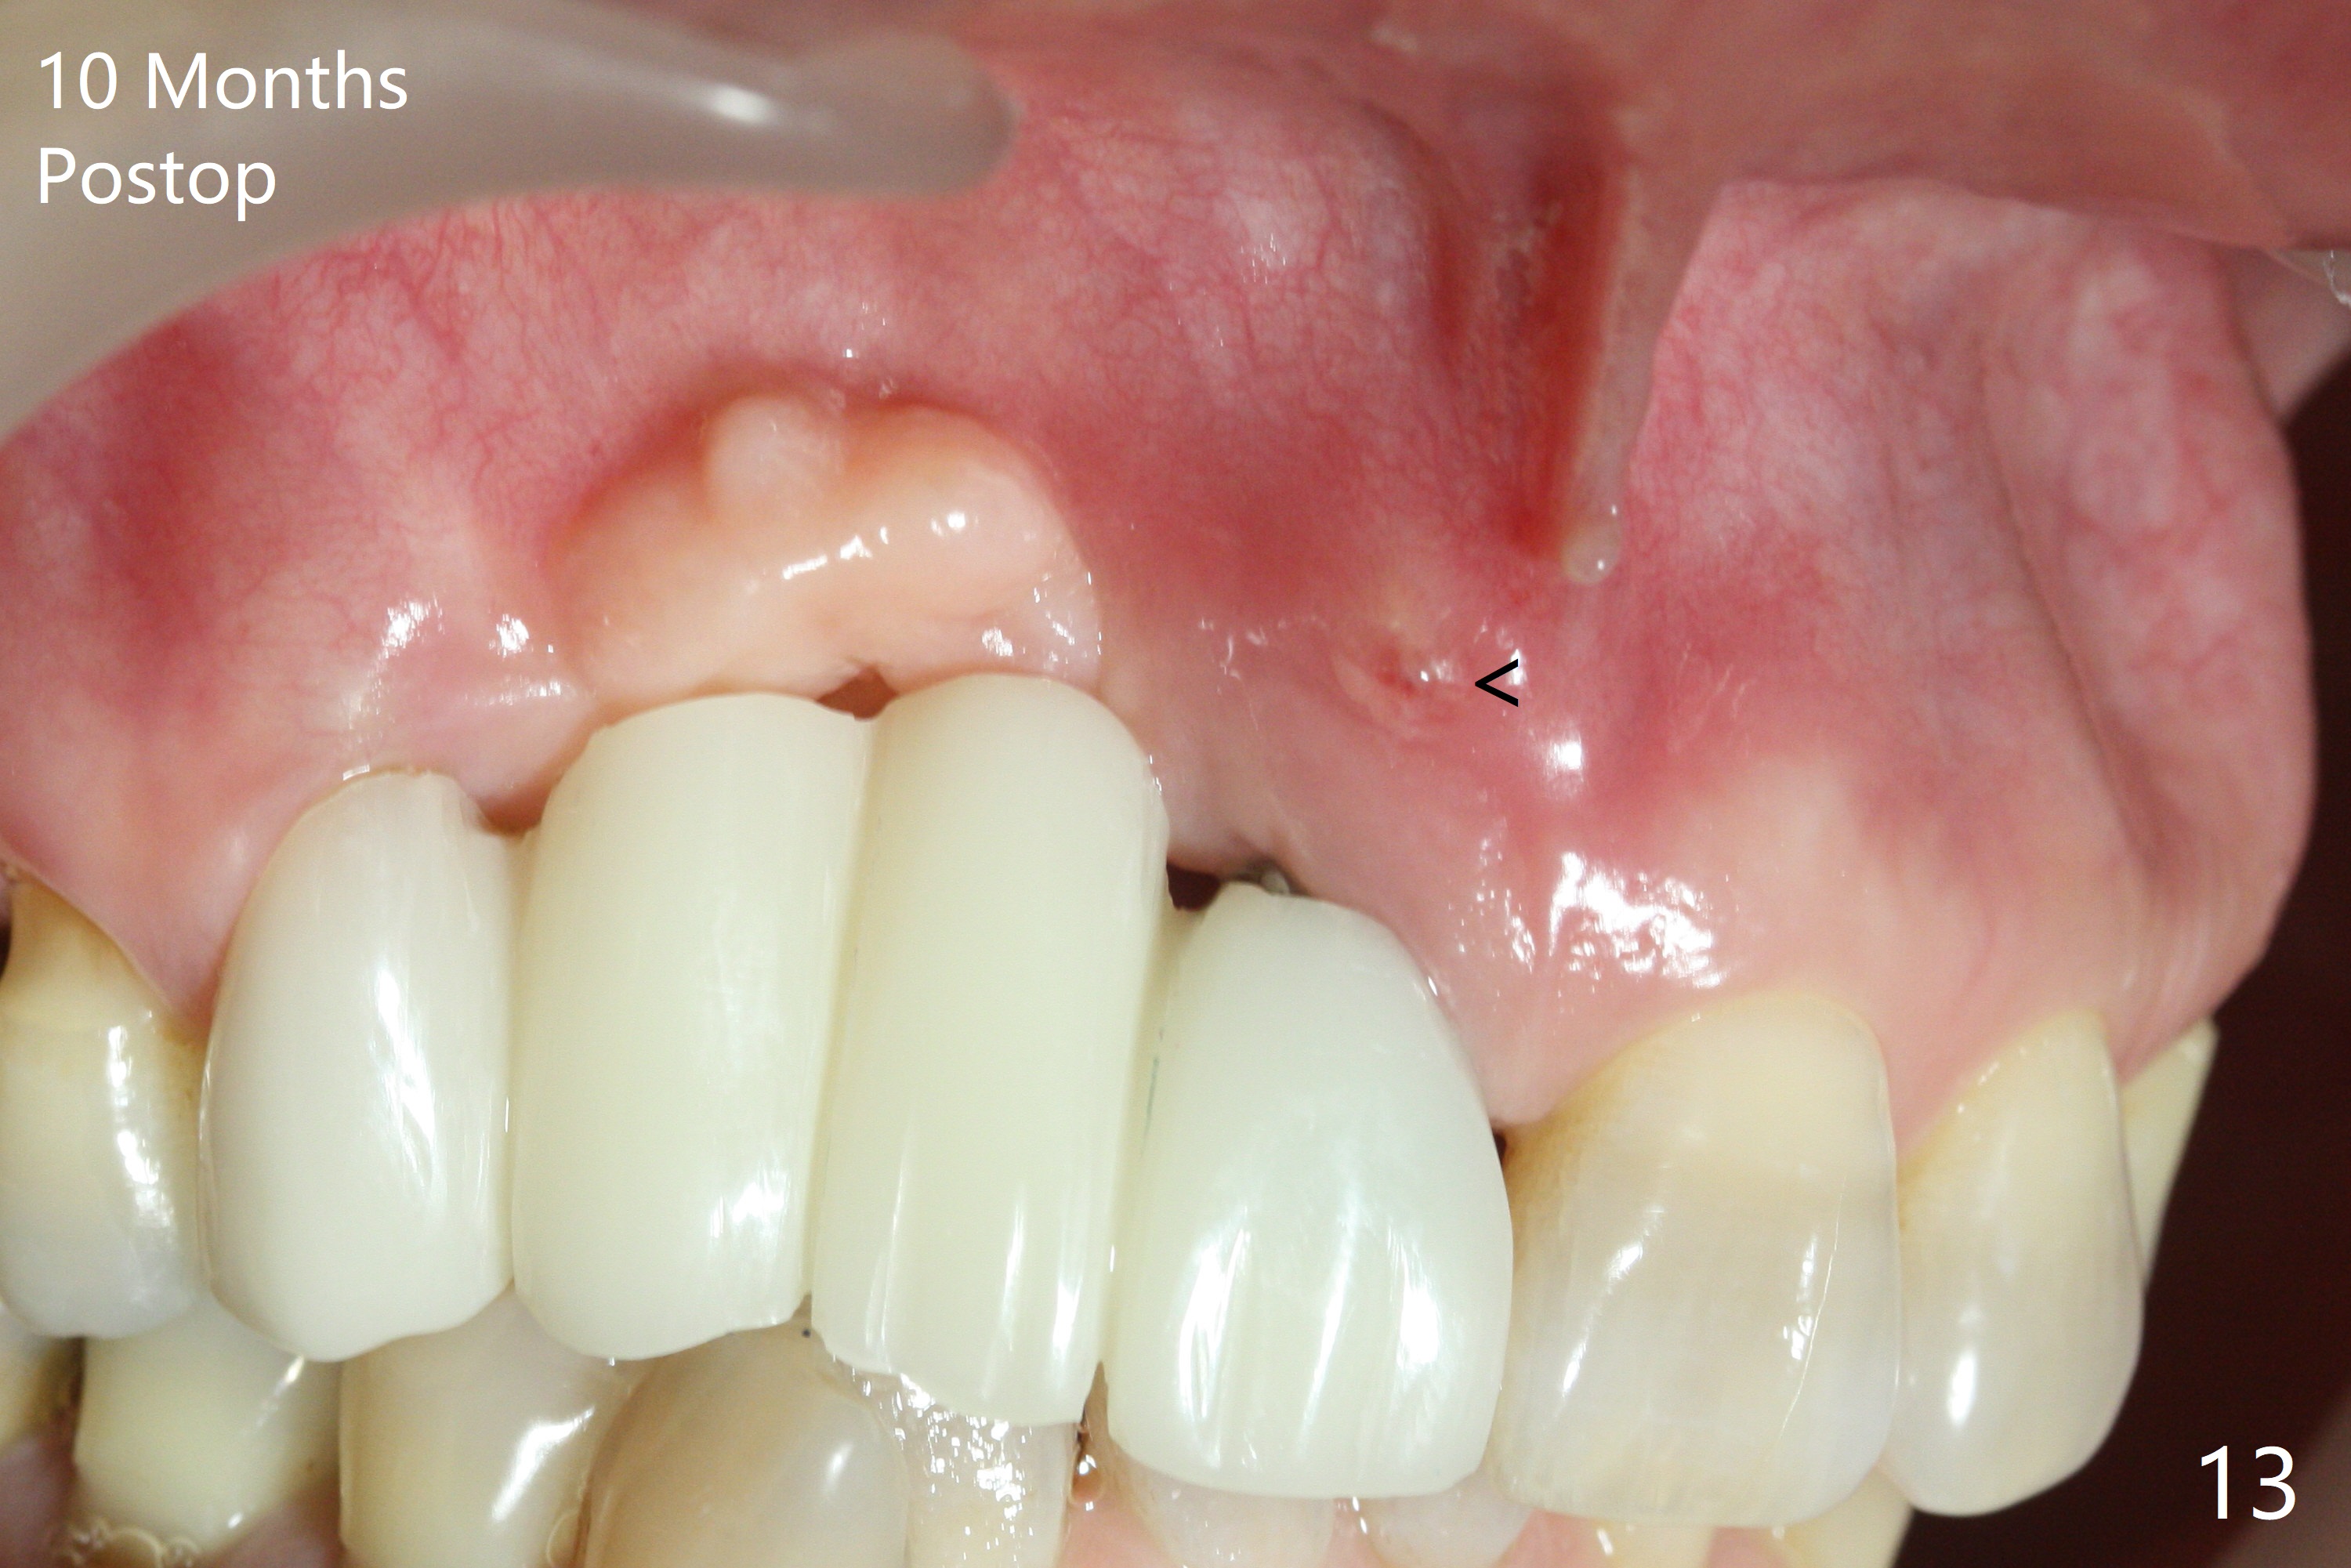

An asymptomatic erythema develops at #8 10 months postop (Fig.12 *). A fistula forms 11 months postop (Fig.13 < ) and is associated with implant thread exposure (Fig. 14 >, as compared to Fig.2). It appears that bone graft and possible block graft are needed with PRF after debridement with Titanium brush.